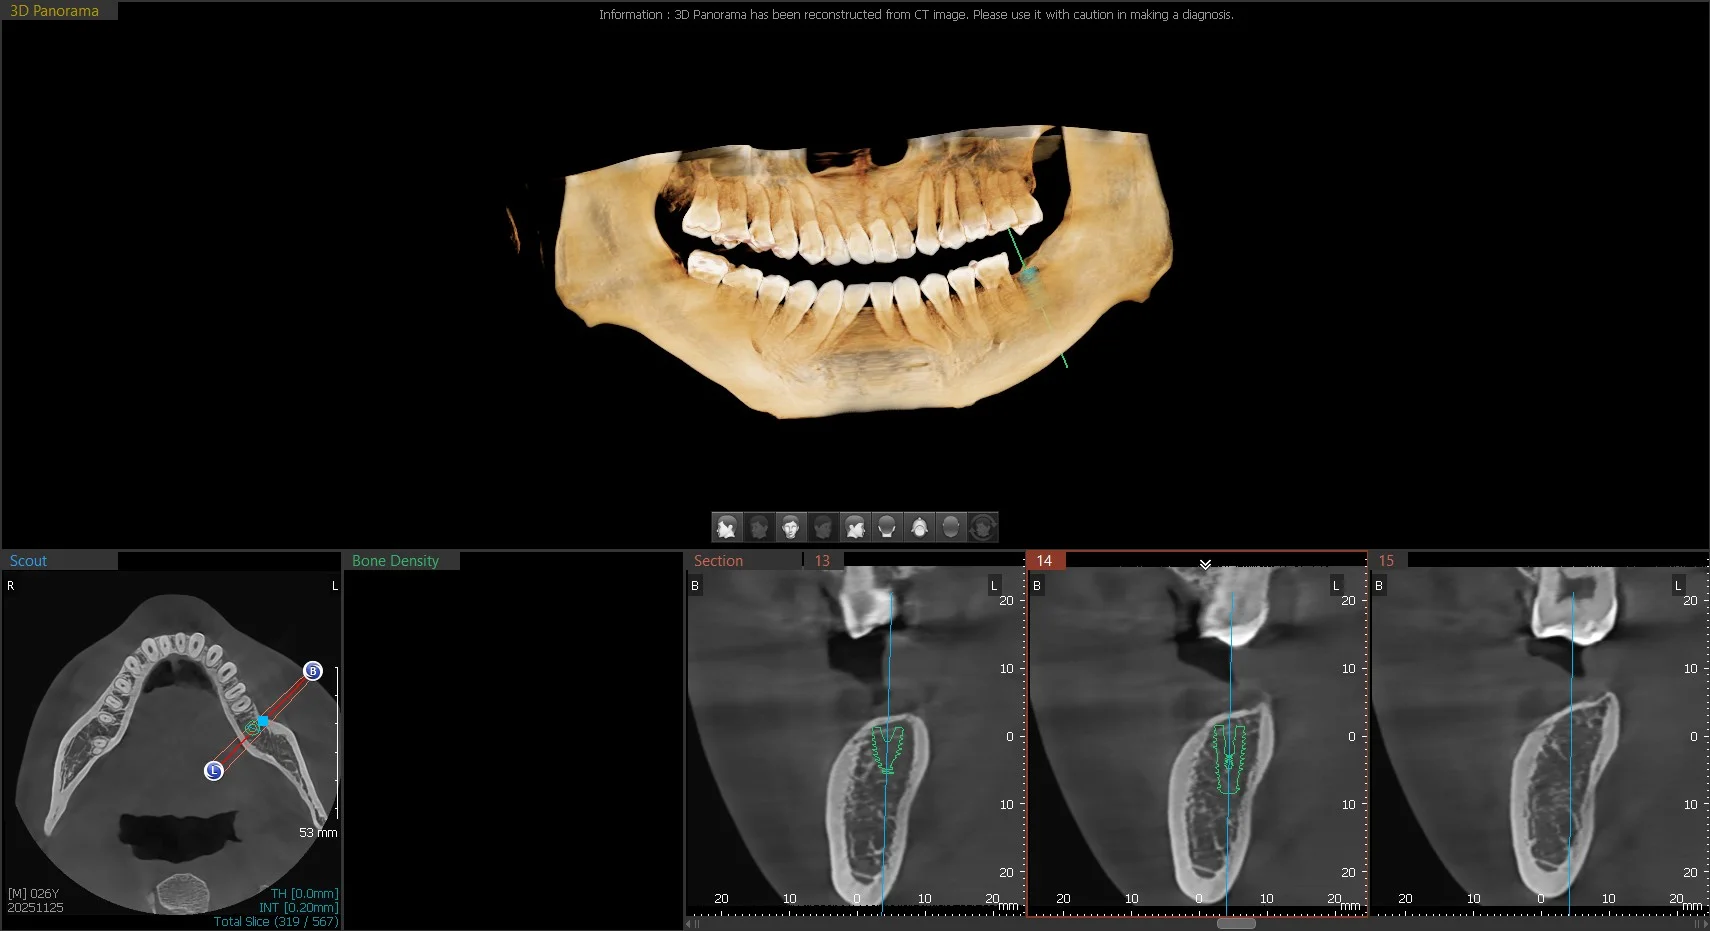

3D reconstructed jaw

Thoughtful Surgical & Restorative Planning

Successful implants require more than placement. We plan the final tooth first — how it will look, how it will function, and how it will distribute bite forces — and then position the implant to support that outcome. Surgical precision and restorative design must work together.

3D Imaging Before We Begin

Every jaw is different. Nerves, sinus spaces, and bone thickness vary from patient to patient. We use CBCT 3D imaging to evaluate your anatomy in detail before placing an implant. This allows us to measure bone quality, identify important structures, and plan placement precisely. Digital scans help us simulate the final result before treatment even begins.